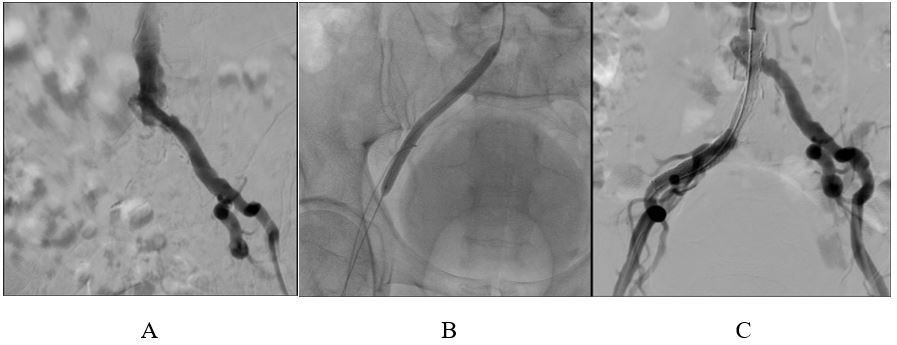

Một trong các ca bệnh đáng chú ý là bệnh nhân N.T., 67 tuổi, tiền sử hút thuốc lá nhiều và tăng huyết áp, vào viện vì tình trạng đau chân nhức chân trái khi nghỉ ngơi, tăng đau khi đi lại làm khó khăn trong việc vận động và ảnh hưởng nhiều đến sinh hoạt hàng ngày. Bệnh nhân được siêu âm doppler mạch máu và chụp mạch số hóa phát hiện tắc hoàn toàn động mạch chậu phải (hình). Sau khi hội chẩn, bệnh nhân đã được thực hiện tiến hành kỹ thuật nong và đặt stent động mạch chậu bên phải. Sau thủ thuật không có biến chứng gì xảy ra, sau vài ngày bệnh nhân đã có sự cải thiện rõ rệt, cơn đau không còn, bệnh nhân có thể đi lại bình thường. Bệnh nhân được cho xuất viện và trở lại sinh hoạt hàng ngày bình thường.

Hình ảnh trước và sau can thiệp của bệnh nhân N.T. 67t. Hình A: tắc động mạch chậu phải, Hình B: tiến hành nong bóng động mạch bị tắc hẹp, Hình C: Sau khi đặt stent Động mạch chậu phải)